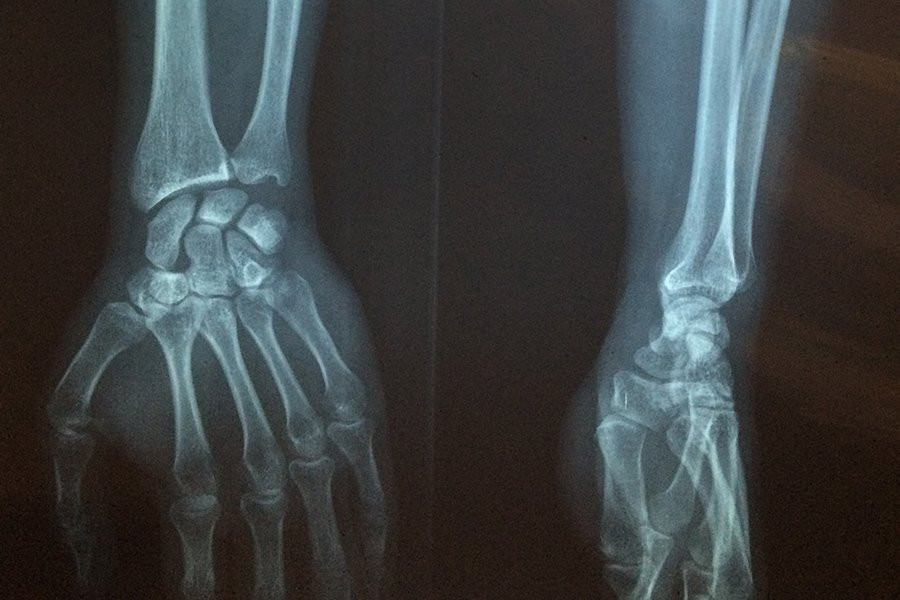

Около половины генома человека состоит из фрагментов ДНК, происходящих от древних вирусов. Теперь известно, что эти «транспозируемые элементы» (TEs) играют различные роли в модуляции экспрессии генов и развитии заболеваний. Теперь международная группа под руководством исследователей KAUST показала, что общий транспозируемый элемент, называемый LINE-1 РНК, играет положительную роль в запуске процесса восстановления костей, с потенциальным применением в лечении остеопороза и многих других заболеваний. Статья опубликована в журнале EMBO Journal.

Во-первых, группа провела эксперименты по секвенированию на мышах с переломами костей и обнаружила, что TEs, особенно РНК LINE-1, были повышены в течение короткого периода времени после перелома.

Затем исследователи изучили TEs в костных клетках (остеобластах), взятых у женщин в постменопаузе с остеопорозом и у здоровой контрольной группы. TEs, в частности LINE, были сильно повышены в здоровых бедренных костях с высокой плотностью костей, в то время как у тех, у кого плотность костей ниже и остеопороз, наблюдалась низкая экспрессия LINE.